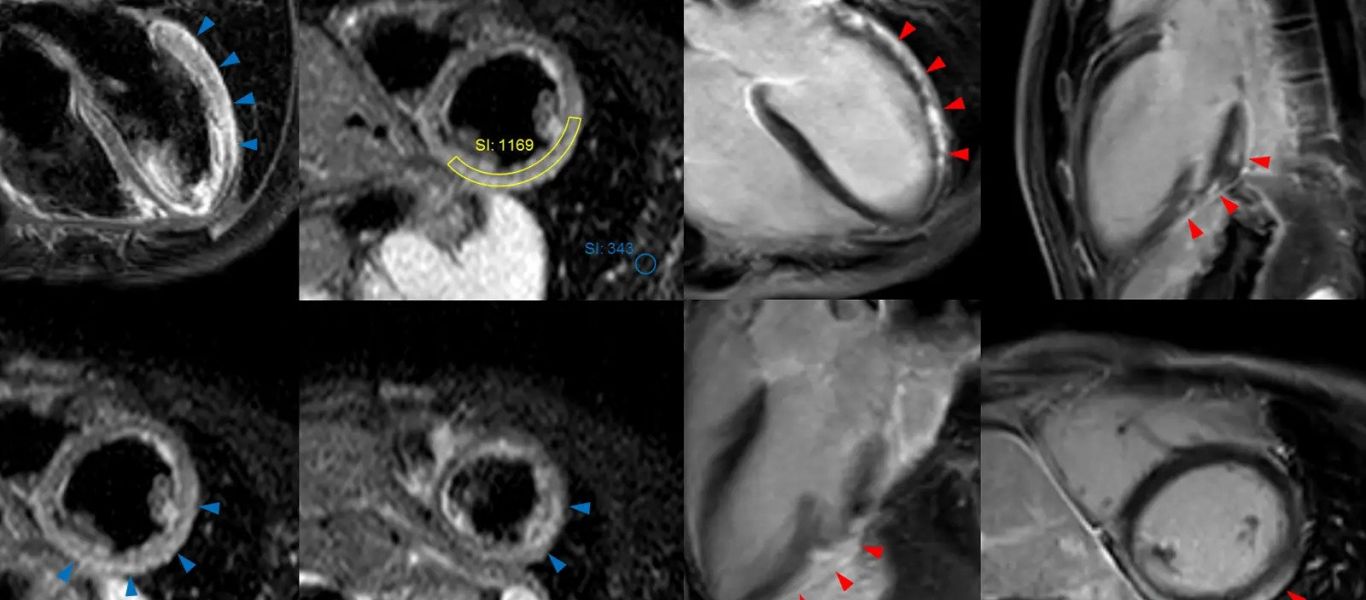

Ανησυχητικά είναι τα στοιχεία από μελέτη που πραγματοποιήθηκε στο Χονγκ Κονγκ τα αποτελέσματα της οποίας δημοσιεύτηκαν στο περιοδικό Clinical Infectious Disease και δείχνουν ότι υπάρχει αυξημένος κίνδυνος εμφάνισης μυοκαρδίτιδας/περικαρδίτιδας μετά τον εμβολιασμό με το εμβόλιο της Pfizer μεταξύ ανδρών και εφήβων, ειδικά μετά τη δεύτερη δόση.

Αυτό που πρέπει να τονιστεί ιδιαιτέρως είναι το γεγονός ότι η νέα κινεζική μελέτη εκτιμά τον κίνδυνο εμφάνισης μυοκαρδίτιδας/περικαρδίτικδας ως και 4 φορές υψηλότερο σε σχέση με τον ευρωπαϊκό οργανισμό ΕΜΑ που παραδέχτηκε επισήμως ότι 1 στους 10.000 εμβολιασμένους με Pfizer θα αναπτύξει μυοκαρδίτιδα/περικαρδίτιδα.Τα στοιχεία που αφορούν τις εκτιμήσεις του ΕΜΑ δημοσίευσε και πάλι πρώτο το Pronews.gr

Η έναρξη της μυοκαρδίτιδας ήταν κατά μέσο όρο 2 ημέρες μετά τον εμβολιασμό. Η κλινικά (οξεία ή ήπια) συχνότητα εμφάνισης μυοκαρδίτιδας/περικαρδίτιδας ήταν μια περίπτωση στους 2.680 εμβολιασμένους. .

Βάσει των δεδομένων της μελέτης 37,32 άτομα ανά 100.000 ή ένας στους 2680 νεαρούς άνδρες παρουσίασε ανάπτυξη μυοκαρδίτιδας/περικαρδίτιδας εντός δύο εβδομάδων από τον δεύτερο εμβολιασμό τους (μέσος χρόνος έως την εμφάνιση του νόσου νόσο: 2 ημέρες μετά τον εμβολιασμό).

Η μυοκαρδίτιδα προκαλεί καρδιακή βλάβη. Η καρδιακή βλάβη είναι εφ’ όρου ζωής – η καρδιά δεν επουλώνεται αντικαθιστώντας τα κατεστραμμένα κύτταρα.

Είναι σημάδια. Οι ουλές στην καρδιά μπορεί να οδηγήσουν σε αλλαγές στην ηλεκτρική αγωγιμότητα στον καρδιακό μυ, που με τη σειρά του μπορεί να οδηγήσει σε «ξαφνικό θάνατο» λόγω αλλαγών στην κανονικότητα των καρδιακών παλμών και της μυϊκής συστολής της καρδιάς. Αυτά τα γεγονότα μπορεί να συμβούν ανά πάσα στιγμή, ιδιαίτερα όταν η καρδιά είναι «πιεσμένη» με κάποιο τρόπο, αναφέρει ο Dr,. Robert Malone.